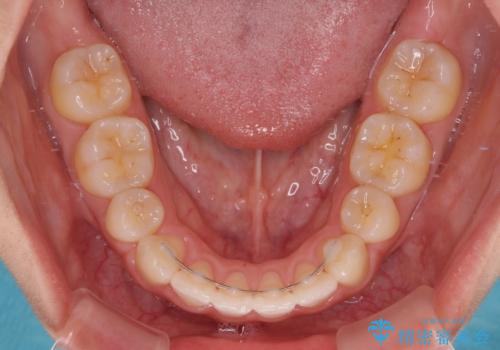

- 矯正装置

- 審美装置

- 2年1ヶ月

4本の歯を抜歯したことで、飛び出していた口元が引っ込み、横顔の印象が大きく改善されました。

- 矯正治療後の保定が不十分だと後戻り(元の位置に戻ろうとする動き)をします